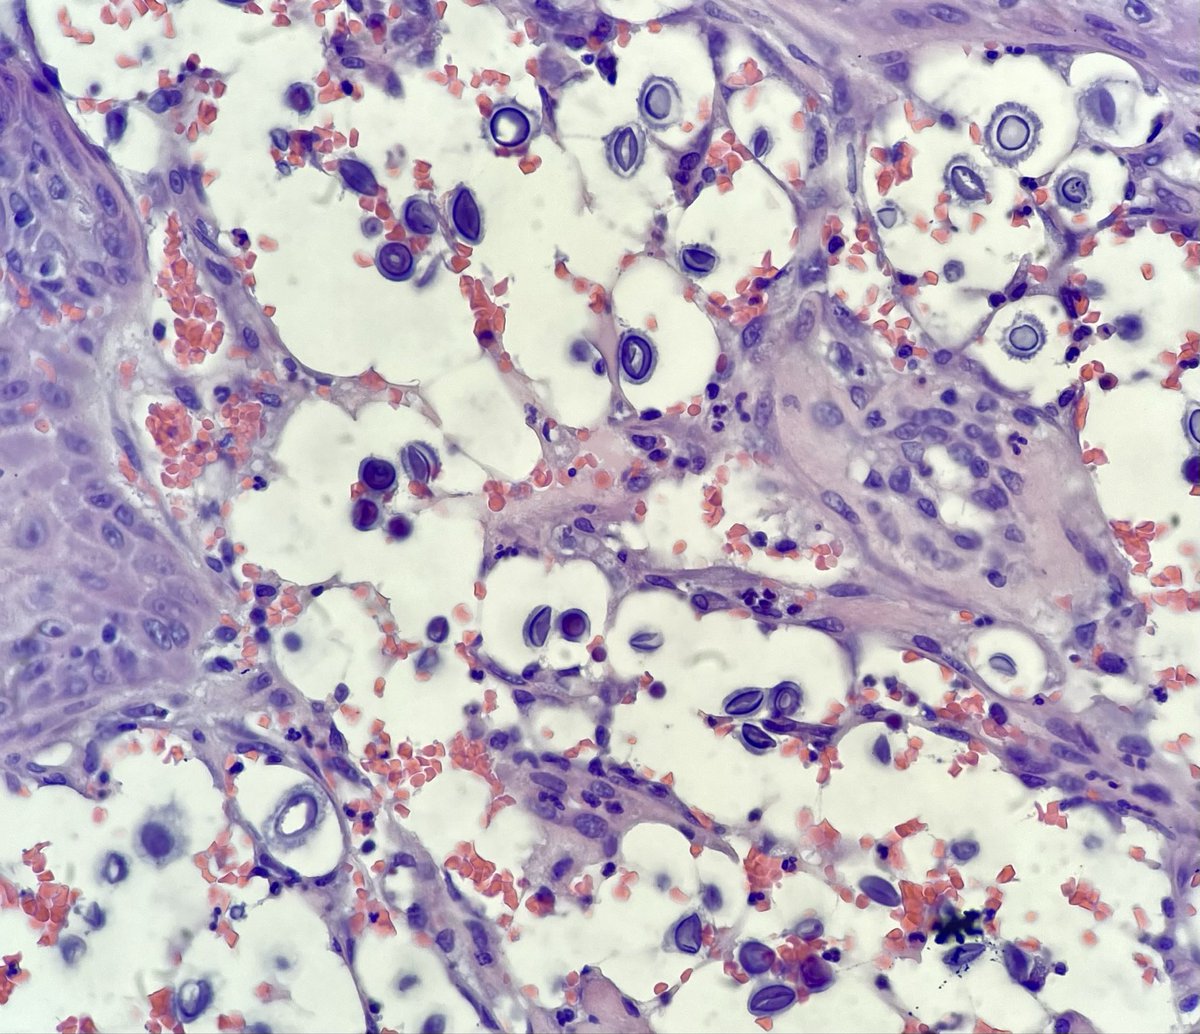

70 yo M no relevant PMH. Buccal mucosa ulcer biopsy (see H&E). Waiting on GMS. Do you buy cryptococcus? @ParasiteGal @LangerPath

AdrianaHogeboom's tweet image. 70 yo M no relevant PMH. Buccal mucosa ulcer biopsy (see H&E). Waiting on GMS. Do you buy cryptococcus? @ParasiteGal @LangerPath